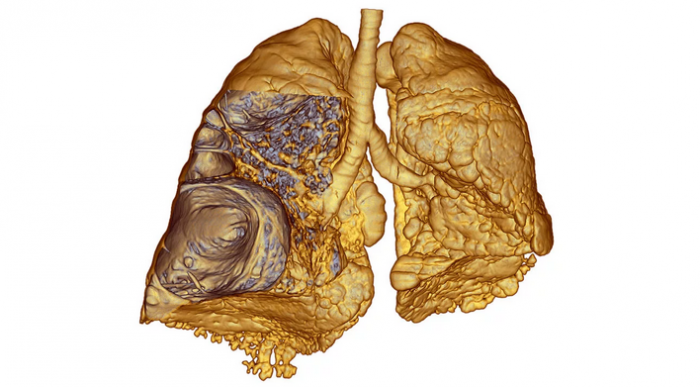

Парасептальная эмфизема легких

Парасептальная эмфизема легкихне будили.